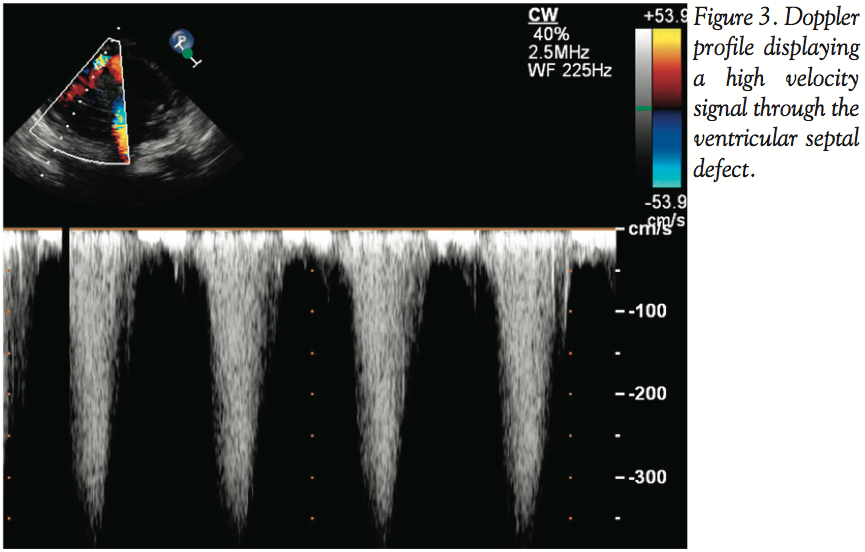

Under general anesthesia, intraoperative transesophageal echocardiogram (TEE) revealed the following pertinent findings: 1) left ventricular function with an ejection fraction of 55%; 2) large true inferior wall aneurysm of the left ventricle (Figure 1); 3) a basal-inferior VSD measuring approximately 1.1 cm in diameter with high velocity signal (Figures 2 and 3); 4) moderately dilated right ventricle with mildly reduced right ventricular function; and 5) moderate tricuspid regurgitation.